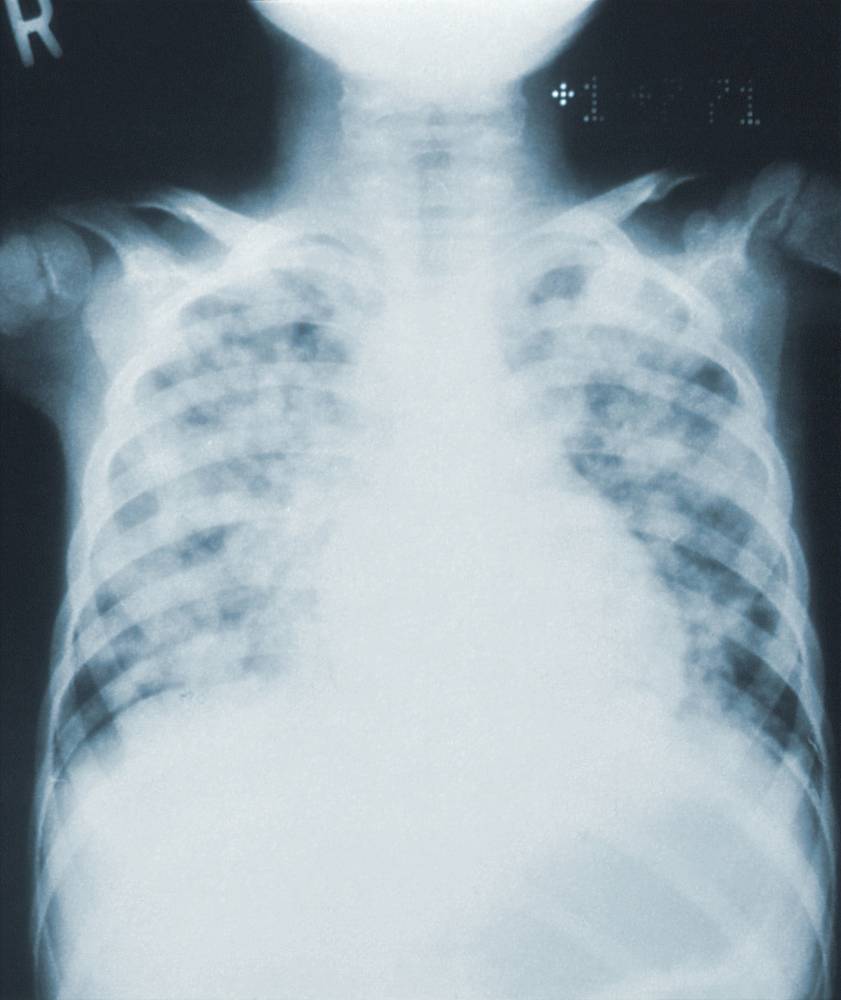

A House leader has sought an investigation in aid of legislation on the alleged unnecessary purchase of costly pneumococcal conjugate vaccines (PCVs), which has purportedly caused billions of pesos in losses to the government. X-ray showing pneumonia. (Cdc/ Unsplash) Probinsyano Ako Party-list Rep....